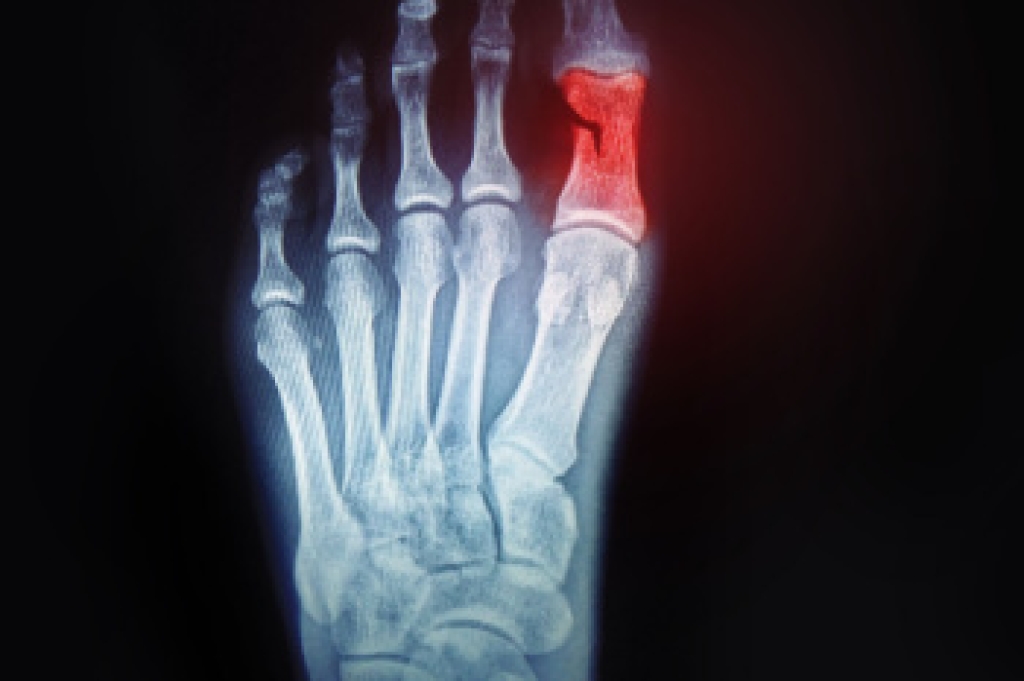

To figure out the cause of foot pain, podiatrists utilize several different methods. This can range from simple visual inspections and sensation tests to X-rays and MRI scans. Prior medical history, family medical history, and any recent physical traumatic events will all be taken into consideration for a proper diagnosis.